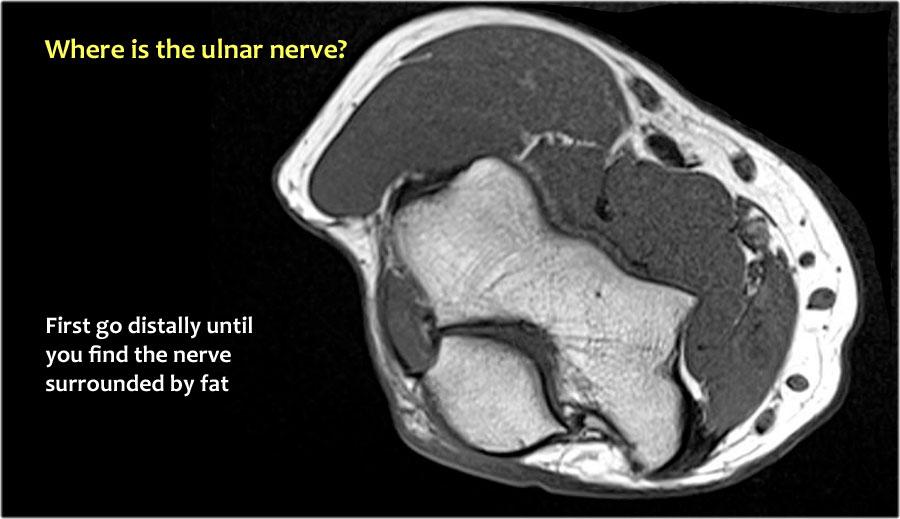

Vì vậy, khi chúng ta quay lại hình ảnh, bạn sẽ nhận thấy rằng có thể khó tìm thấy dây thần kinh.

Bất kỳ cấu trúc dưới da nào trong số này đều có thể là dây thần kinh đã được chuyển vị.

Một cách để thực hiện là đi theo các cấu trúc về phía xa cho đến khi tìm thấy dây thần kinh trụ ở phía xa tại vị trí bình thường của nó ở vùng cẳng tay gần được bao quanh bởi mô mỡ.

Sau đó khi bạn theo dõi nó về phía gần, bạn sẽ nhận thấy rằng đây là một trường hợp chuyển vị dưới da.